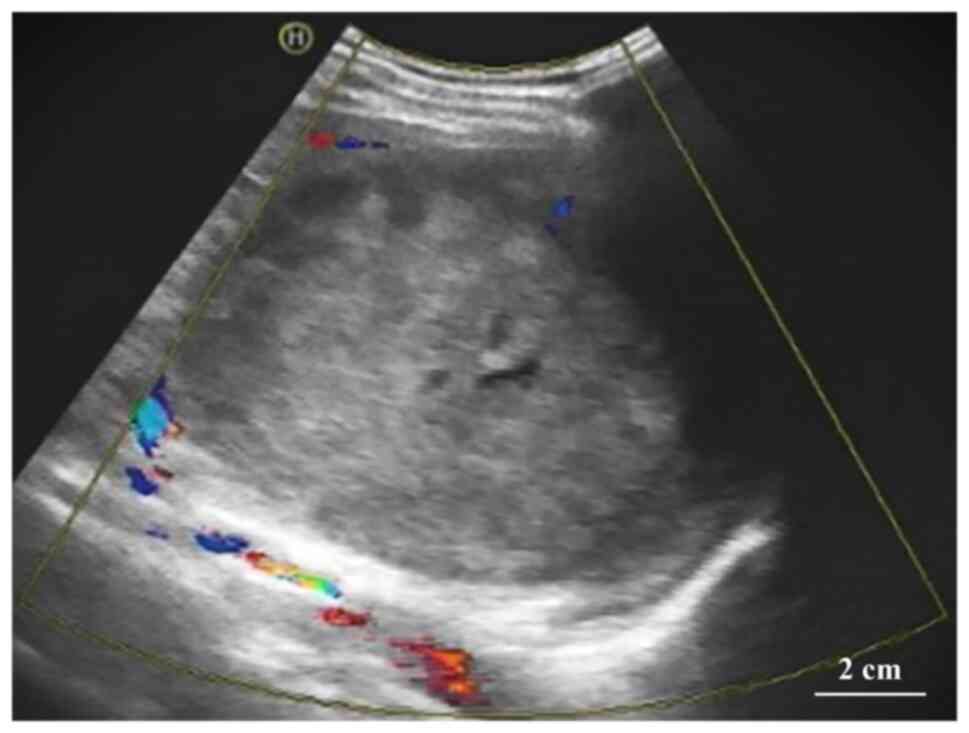

The CT of the abdomen revealed a mass of heterogeneous density with patchy, slightly hyperdense and poorly defined borders. In addition, punctate calcification was observed in the tumor. The parenchymal portion of the tumor had progressive enhancement, whereas the central liquefied necrotic region exhibited no discernible enhancement. The boundary between the tumor and the surrounding tissue was visible following enhancement (Fig. 2). Abdominal CT displayed a slightly hypodense, ill-defined mass. In addition, small patchy hemorrhage as well as calcification were seen within the mass (Fig. 2). Abdominal magnetic resonance imaging (MRI), including conventional MRI and enhanced abdominal MRI, indicated a mixed-signal mass in the spleen, measuring ~10.6×10.6×10.1 cm, with well-defined borders. The tumor margin had an envelope-like structure and the parenchyma exhibited progressive enhancement with no enhancement in the central necrotic area. The parenchymal part of the neoplasm had a high signal (b=1,000 sec/mm2) on diffusion-weighted imaging (DWI) and a low signal on the apparent diffusion coefficient map, suggesting that the spread of the parenchymal part of the neoplasm was restricted; by contrast, the central necrotic area was not restricted (Fig. 3). The radiologist initially diagnosed a vascular tumor originating from the spleen, such as hemangioma, based on this patient's clinical presentation and the imaging features. However, it was not possible to exclude other benign or malignant neoplastic lesions.

Figure 2.

(A) On the plain CT scan, the poorly defined tumor was visible as a foveal hypodense area with a noticeable occupying effect; small patchy high-density hemorrhagic foci and punctate calcifications may be seen within the tumor (arrow). (B) CT-enhanced arterial phase indicates the parenchymal part of the spleen tumor was mildly enhanced with foveal changes and abundant distribution of small arteries may also be seen in the parenchymal part. (C) In the CT-enhanced venous phase, the parenchymal part of the tumor was further enhanced but the density of the parenchymal part of the tumor was still smaller than the normal parenchymal part of the spleen. (D) CT-enhanced delayed period indicates the parenchymal part of the tumor further intensified with a density equal to that of the normal parenchymal part of the spleen, while the central liquefied necrotic area was never enhanced (scale bar, 2 cm).